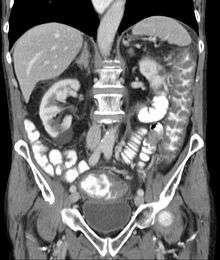

| Pathological specimen showing pseudomembranous colitis | |

Prior to the advent of tests to detect C. difficile toxins, the diagnosis most often was made by colonoscopy or sigmoidoscopy. The appearance of "pseudomembranes" on the mucosa of the colon or rectum is highly suggestive, but not diagnostic of the condition.[25] The pseudomembranes are composed of an exudate made of inflammatory debris, white blood cells. Although colonoscopy and sigmoidoscopy are still employed, now stool testing for the presence of C. difficile toxins is frequently the first-line diagnostic approach. Usually, only two toxins are tested for—toxin A and toxin B—but the organism produces several others. This test is not 100% accurate, with a considerable false-negative rate even with repeat testing.